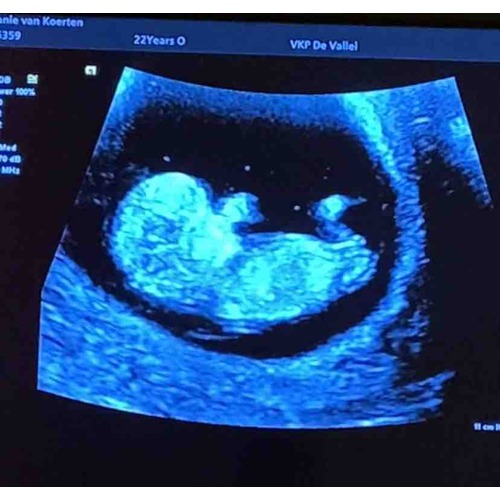

Is er iemand die hier iets uit kan halen qua geslacht?

Wat denken jullie?馃グ馃挏 12wk6

Wat denken jullie 馃槉馃槉鉁ㄢ湪